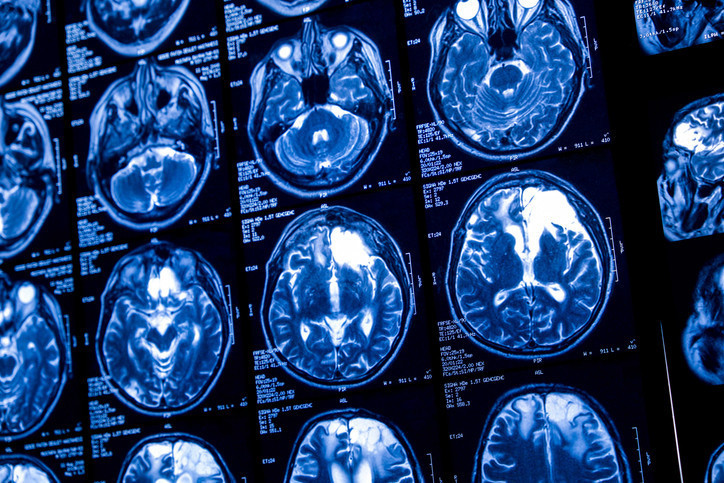

Zihinsel yorgunluk, odaklanma güçlüğü ve unutkanlık çoğu zaman yoğun tempoya bağlansa da, bilimsel veriler bu şikâyetlerin beslenme alışkanlıklarıyla yakından ilişkili olabileceğini gösteriyor.

Yüksek oranda işlenmiş gıdalar, düzensiz kan şekeri dalgalanmaları, mikro besin eksiklikleri ve yetersiz sıvı alımı; beyin fonksiyonlarını olumsuz etkileyerek beyin sisi tablosunu tetikleyebiliyor. Buna karşılık antiinflamatuvar ve antioksidan yönü güçlü, dengeli bir beslenme modeli bilişsel performansın korunmasında önemli bir rol oynuyor.

Beslenme ve Diyet Uzmanı Zehra Elban, “Beyin sağlığı yalnızca uzun vadeli hastalık riskleriyle değil, günlük zihinsel performansla da doğrudan ilişkilidir; doğru beslenme, zihinsel berraklığın en temel destekçilerinden biridir” dedi, beyne zarar veren ve iyi gelen besinleri anlattı.

Oysa literatürde beyin sisi olarak tanımlanan bu tablo, tek başına bir hastalık değil; beslenme düzeni ve yaşam tarzıyla yakından ilişkili bir sinyal olarak değerlendirilmelidir. Güncel bilimsel çalışmalar, özellikle beslenme içeriğinin bilişsel işlevler üzerinde doğrudan ve ölçülebilir etkileri olabileceğini gösteriyor.